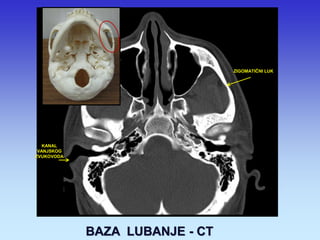

BAZA LUBANJE - CT

ZIGOMATIČNI LUK

KANAL VANJSKOG ZVUKOVODA